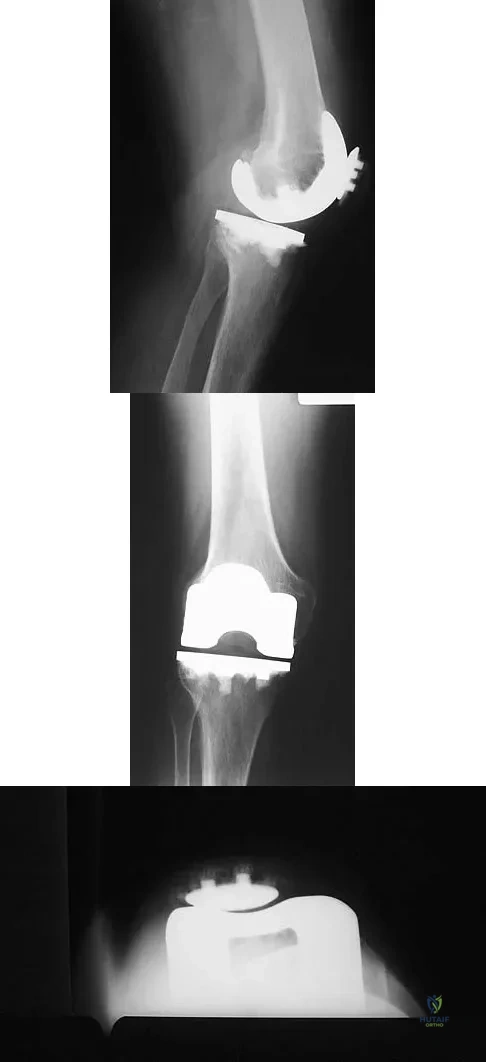

A 77-year-old woman who underwent total knee arthroplasty 16 years ago now reports pain, swelling, and notable crepitation with range of motion. AP, lateral, and Merchant radiographs are shown in Figures 54a through 54c. What is the most likely diagnosis?

Explanation